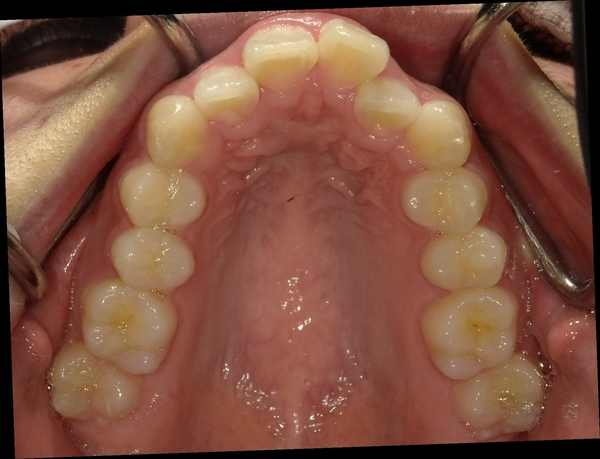

ガタガタとした歯並びや八重歯(叢生)CASE51